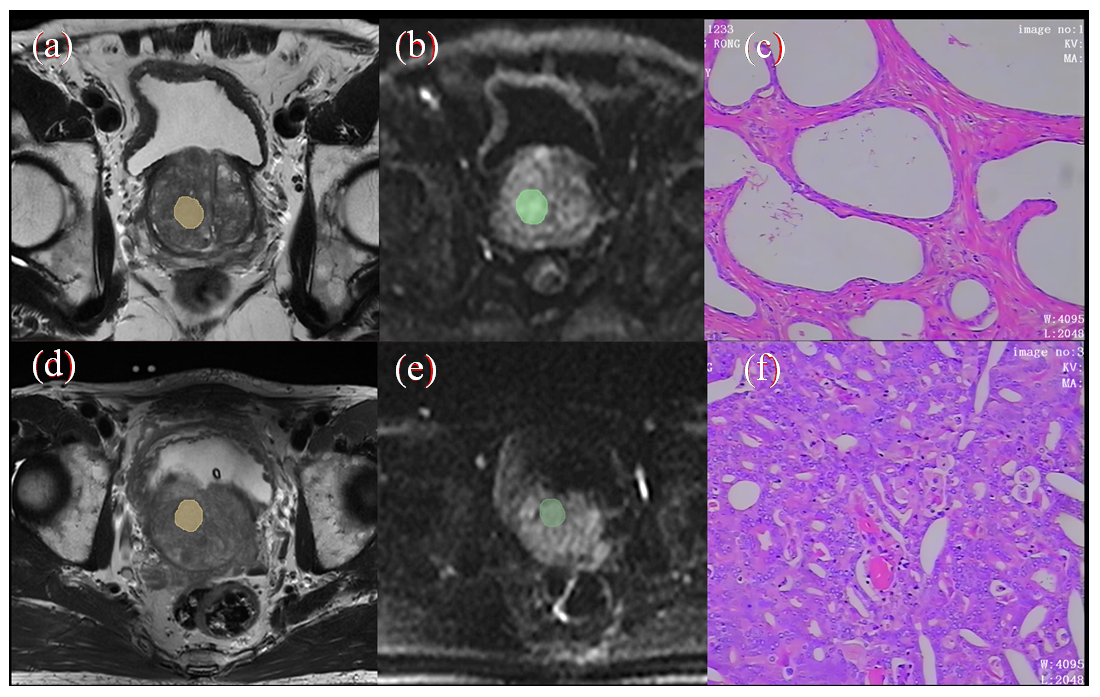

基于T2WI与DWI多参数MRI纹理特征融合的前列腺癌预测模型构建

前列腺癌(PCa)是男性最常见的癌症之一,影像学检查已逐渐应用于其诊断中. 本研究基于磁共振T2加权成像(T2WI)联合扩散加权成像(DWI)纹理特征分析构建PCa模型分析.筛选出差异显著的特征参数构建PCa预测模型,利用受试者工作特征(ROC)曲线及曲线下面积(AUC)明确纹理特征对疾病鉴别诊断价值.结果表明,将方差T2WI、平均值DWI构建PCa预测模型,AUC值为0.994,具有较高的预测价值.证明基于T2WI与DWI的纹理特征构建预测模型对鉴别PCa有较好应用价值.

Prostate cancer (PCa) is one of the most common cancers in men, and imaging techniques have been increasingly used in its diagnosis. This study develops a prostate cancer model based on magnetic resonance T2-weighted imaging (T2WI) combined with diffusion-weighted imaging (DWI) texture analysis. Significant feature parameters were selected to construct a predictive model for prostate cancer, and the diagnostic value of texture features for disease discrimination was evaluated using the receiver operating characteristic (ROC) curve and the area under the curve (AUC). The results showed that the prostate cancer prediction model incorporating ${\sigma }_{\text{T2WI}}^{\text{2}}$ and ${\mu }_{\text{DWI}}^{}$ achieved an AUC value of 0.994, demonstrating high predictive performance. This study confirms that the textural features based on T2WI and DWI have good application value in distinguishing prostate cancer.